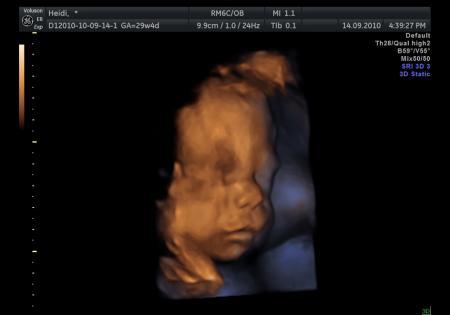

und hier noch ein 3D Bild

Bild zu